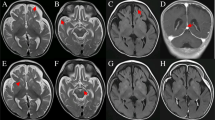

The pedigree underwent careful physical examination. The proband’s parents (I:1, I:2) were nonconsanguineous and both appeared normal. The proband (II:1) had frequently suffered from pneumonia since she was born, accompanied with shortness of breath much of the time (Fig. 1A). As a neonate, she presented laryngeal stridor and was diagnosed with laryngomalacia. She began to experience nausea and vomiting after being fed when she was 2 months old, and a gastrostomy tube was placed at that time. She presented considerable tympanites and gastrointestinal dysmotility with frequent vomiting. When she was 6 months old, she could raise her head. She could sit at the age of 10 months and stand at the age of 2 years. Developmental delay was obvious at the age of 4 years, when she reached a height of only 98cm (<2SD). Unfortunately, the patient suffered from motor retardation. Furthermore, she was unable to sit or stand without help, let alone walk. Moreover, muscular hypotonia and exercise intolerance was evident. Her motor development, speech, and social adaptation were assessed to be 2.5 years delayed. She only could communicate with her family by facial expressions, gestures, and simple sounds even though she had normal visual and auditory abilities. Recurrent seizures appeared with spastic diplegia at 5 years of age. A prominent fast wave in the frontal lobe was observed by electroencephalogram examination. Brain magnetic resonance imaging (MRI) showed a wide extracerebral space (Fig. 1B) and thin corpus callosum (Fig. 1C). Muscle biopsy showed myopathic changes with different size and small diameter of muscle fibers (Fig. 1D), and increased lipid droplets (Fig. 1E). Additionally, hepatic biopsy followed by electron microscopy revealed abundant lipid droplets (Fig. 1F). Through light microscopy, diffuse hepatocellular steatosis was observed (Fig. 1G). Immunohistochemistry showed that the bile duct epithelium was positive for cytokeratin 19 (Fig. 1H) and a few activated Kupffer cells were positive for CD68 (Fig. 1I), and Masson staining revealed fibrous hyperplasia in the portal area (Fig. 1J). Due to intracytoplasmic accumulation of glycogen, the periodic acid-Schiff (PAS) reaction was positive (Fig. 1K) and the D-PAS reaction was negative (Fig. 1L). In addition, blood tests indicated mildly elevated alanine aminotransferase levels and a physical exam did not indicate hepatomegaly. There was an apparent renal defect with oliguria and elevated creatinine, urea nitrogen, and uric acid levels, so dialysis was employed. Inherited metabolic disorders were screened, and slightly elevated lactate levels in blood and urine were observed. Serum antibody tests for toxoplasma, rubella virus, cytomegalovirus, and herpes simplex virus were negative and the patient’s plasma ammonia levels, triglyceride levels, blood glucose levels, karyotype, auditory brainstem responses, and thyroid function were all normal. There was no cardiac involvement apart from tachycardia; cardiac troponin I and creatine kinase isoenzyme levels were also in the normal range (Table 2). The patient died from stroke and respiratory failure at the age of 5 years. According to the patient’s main symptoms, which were in accordance with the common features of COXPD26, a diagnosis of COXPD26 was made.

The clinical and histopathological examination. A Pneumonia indicated by X-ray result. B and C Abnormality in the brain with wider extracerebral space and thinner corpus callosum. D Myopathic changes with different size, small diameter of muscle fibers were observed by HE staining and E increased lipid droplets by oil staining (10×). F Hepatic biopsy showed abundant lipid droplets by electron microscopy. G Diffuse hepatocellular steatosis was observed in liver through light microscope; H Immunohistochemistry showed that the bile duct epithelium was positive for cytokeratin 19; I a few activated Kupffer cells were positive for CD68; J Masson staining showed fibrous hyperplasia in the portal area; K PAS reaction in liver was positive due to intracytoplasmic accumulation of glycogen; L D-PAS was negative in liver. All figures of liver by light microscope were showed with 20×

Our case presented recurrent pneumonia, shortness of breath, gastrointestinal dysmotility with frequent vomiting, severe developmental delay, muscular hypotonia and exercise intolerance, and renal and hepatic defects. She was unable to sit or stand without help. In addition, her motor development, speech, and social adaptation were delayed, which is consistent with previous reports [1,2,3]. Recurrent seizures with spastic diplegia appeared when she was 5 years old, which is consistent with Patient 2 in Mark’s article [3]. A wide extracerebral space and thin corpus callosum were indicated by brain MRI. Brain MRI of this disease is not specific, as each patient has different manifestations. Muscle biopsy showed myopathic features without ragged-red fibers, as was the case for the 7-year-old patient in Powell’s paper [2]. Muscle biopsy also indicated reduced respiratory chain complex enzyme activities. Unfortunately, the enzyme activity of COX could not be detected in our lab. However, liver pathology of this disease has not been reported in previous research. In the present study, light and electron microscopy indicated a large amount of glycogen and high fat accumulation in the liver, which likely led to liver damage with increased collagen deposition and Kupffer cell activation. Blood glucose levels were within the normal range, but the patient’s delayed motor development and exercise intolerance indirectly suggested mitochondrial complex deficiency, as previously reported in other cases [1,2,3], eventually leading to reduced glycogen utilization, followed by the conversion of excessive glycogen into fatty acid, which manifested as increased fatty acid levels in the liver and muscle tissue.